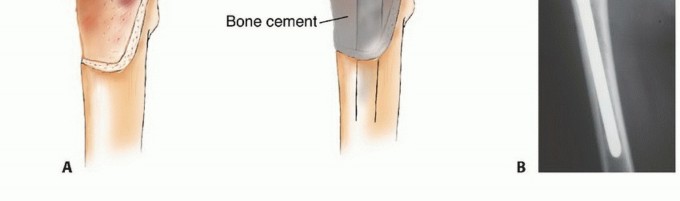

الشكل 1: أ. صورة أشعة سينية تظهر ورمًا نقيليًا في الحُق الأيمن لدى رجل يبلغ من العمر 72 عامًا ولديه تاريخ معروف بسرطان الغدة الدرقية. ب. يظهر التصوير المقطعي المحوسب (CT) تدميرًا واسعًا للعظام وامتدادًا للأنسجة الرخوة. محاولة الاستئصال بناءً على النتائج الشعاعية وحدها قد تؤدي إلى استئصال جزئي للآفة ونزيف محتمل بسبب الأوعية الدموية الكثيفة لهذا الورم. بالنظر إلى هذه النتائج الشعاعية، خضع هذا المريض لانسداد وعائي قبل الجراحة مما قلل من فقدان الدم أثناء الجراحة وسمح باستئصال ناجح.

الشكل 2: أ. صورة أشعة سينية تظهر كسرًا مرضيًا في الورك لدى أنثى تبلغ من العمر 69 عامًا ولديها تاريخ معروف بسرطان الثدي. ب. أجريت عملية استبدال نصفي للورك خلال 24 ساعة من حدوث الكسر، ولكن صور الأشعة السينية بعد الجراحة أظهرت نقيلة إضافية أسفل طرف جذع الطرف الاصطناعي (ج) لم يتم اكتشافها بسبب سوء جودة صور الأشعة السينية قبل الجراحة ولأن صور الأشعة السينية للعظم بالكامل لم تُجرَ قبل الجراحة. د. بينما كانت لا تزال في المستشفى، عانت من كسر مرضي في تلك الآفة أثناء نقلها من سريرها إلى كرسي استلقاء.